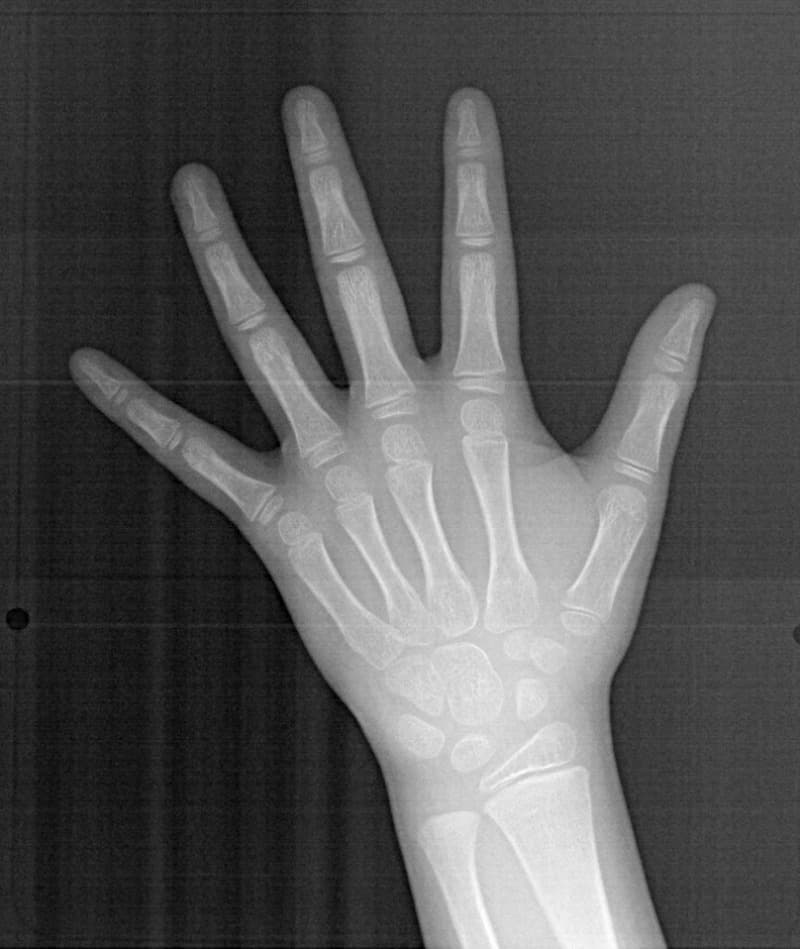

FX(フェイシャルアキシス)は85度なので東洋人の平均値に近く、下顎が前方に過剰成長するリスクは強くはありません。

しかしやはり上顎は劣成長で、下顎が優位な状態ではあります。

上下顎のギャップはありますが、顔面自体の幅径は良好な値を示していますので、スペース不足は拡大することによって解決できポテンシャルはあると考えられます。

左右の非対称もさほど強くありません。

骨年齢は実年齢よりも低めなので、今後下顎の旺盛な成長が見込まれます。

検査時のレントゲン分析では、上下顎の関係は、上顎の劣成長があり下顎前突傾向という値がでておりましたが、前歯ジャンプ後はフェイスマスクの効果もあり、上下顎の関係は正常化しています。

上顎が若干優位になっていますので、今後の下顎の成長のための貯金になっているくらいです。